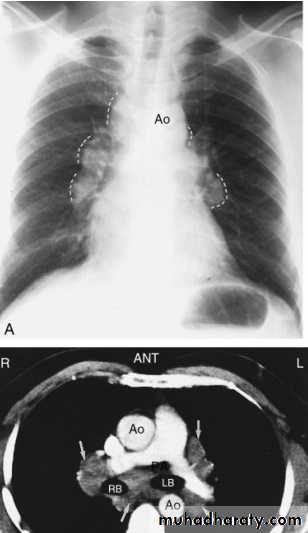

Thymoma.

A chest x-ray (A) reveals an unusual contour over the left hilum (arrows). That the hilum is not obscured (no silhouette sign) indicates that the mass must either be in front of or behind the hilum. A computed tomography scan (B) reveals a soft tissue mass (arrow) just to the left of the aorta. This is the most common location of a thymoma.